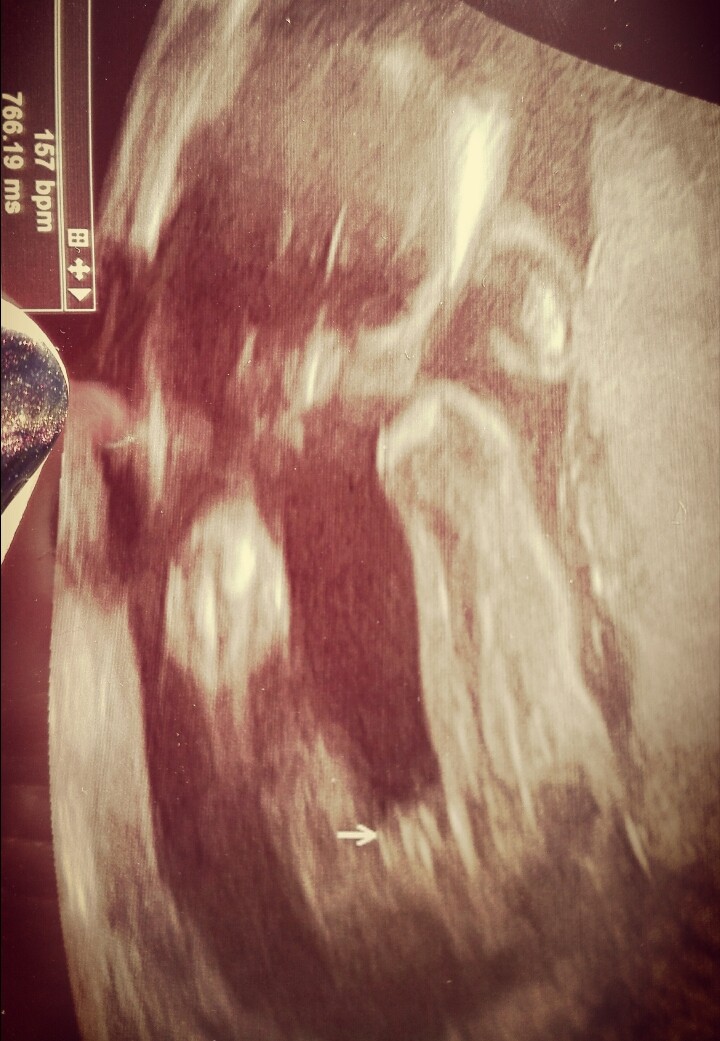

nie jest to najaktuakniejsze zdjęcie bo to screen z filmiku z któryś badań, ale za każdym razem tak wygląda

Rzeczywiście jest luka między wargami. I wygląda jak część kobieca nie siusiak :D ciężko by było chyba się pomylić przy takim widoku :D

Klaudia, wiem, ze nie do mnie pytanie ;) u mnie na zdjeciu dzidzi tak wyglądają miejsca intymne córki, tak jak ta strzaleczka pokazuje.Zobacz załącznik 842414

Dziękuje :) napatrze się na miejsca intymne waszych córek to będzie mi łatwiej rozróżnić mojej :D